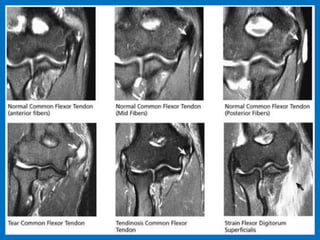

Medial epicondylitis (Golfer's elbow). Coronal fat-suppressed proton

density-weighted MR images . On the left image, a partial tear of

the common flexor tendon (white arrow) is observed. On the right

image, the common flexor tendon origin is usually thickened and

shows increased signal intensity (yellow arrow).Note the presence of

subtle bone marrow edema in the medial epicondyle (blue arrow).